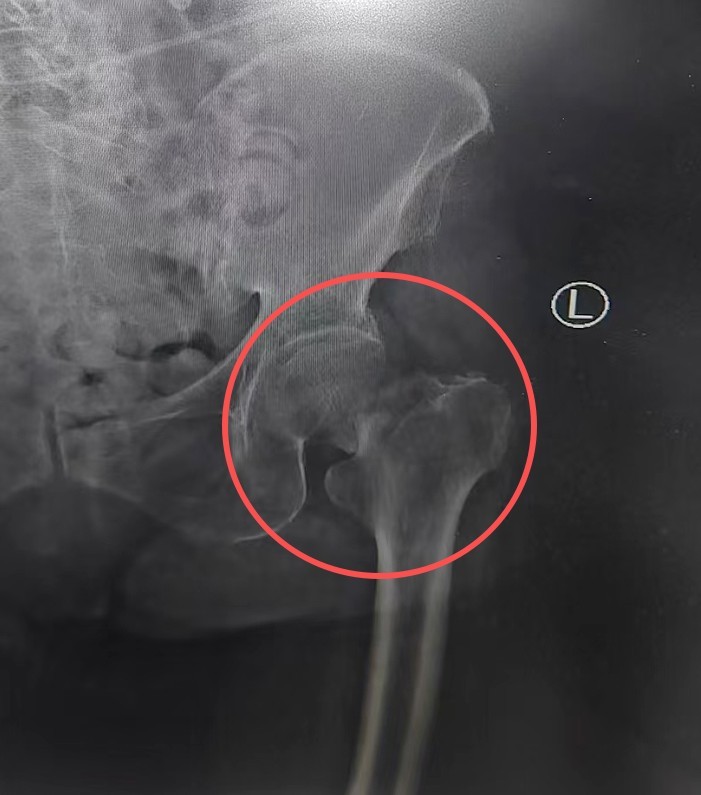

7小时前,刘奶奶在家中不慎摔倒,左髋部剧痛,动弹不得。家人火速将老人送至当地医院,X线检查显示:左侧股骨颈骨折。这个诊断对年轻人尚属严重,对97岁高龄的老人更是危及生命的重创。

刘大诚主刀,杨效宁主任全程指导,主治医师孙一公、宋子鉴担任助手。刘大诚娴熟地将患者已经骨折的股骨头取下,然后精准选取合适的股骨头假体为患者安装。安装完成后,他仔细检查髋关节各项活动,确认关节活动不受影响、稳定性佳、匹配度良好不脱位。